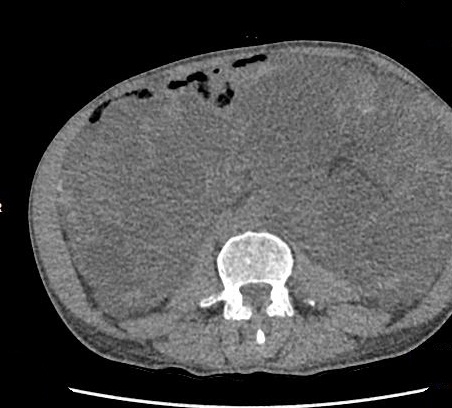

A 49-year-old male patient was diagnosed with ADPKD while the evaluation of urinary tract infection in 2010. Renal failure progressed quickly in the patient after the diagnosis of polycystic kidney disease. Renal replacement therapy was begun due to end-stage renal failure in June 2013. His father was also a dialysis patient secondary to ADPKD. The patient was too slim with 56 kg weight and 18.9 BMI. Physical examination revealed that the abdomen was distended because of the polycystic kidneys. He said that he suffered from nutritional problems due to gastro-intestinal disturbances and vomiting secondary to the pressure of the kidneys. Computed tomography revealed giant polycystic kidneys covering most of the abdominal space (Figure 1a, 1b).

Figure 1a. Axial view of the abdominal tomography

Figure 1b. Coronal view of the abdominal tomography. Huge polycystic kidneys are visible and the intestinal

structures are deplaced to the caudally. There are also multiple cysts in the liver